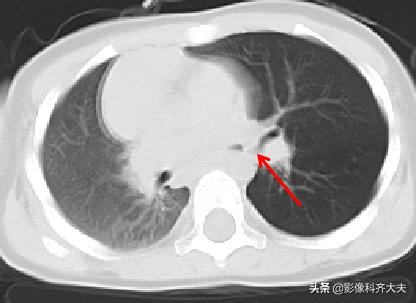

病例1、病史:患儿,女,一岁半,咳喘两周,病前有“开心果”吸入史。

图为轴位及冠状位重建图显示异物:红色箭头为异物的位置,冠状位显示尤为清晰。